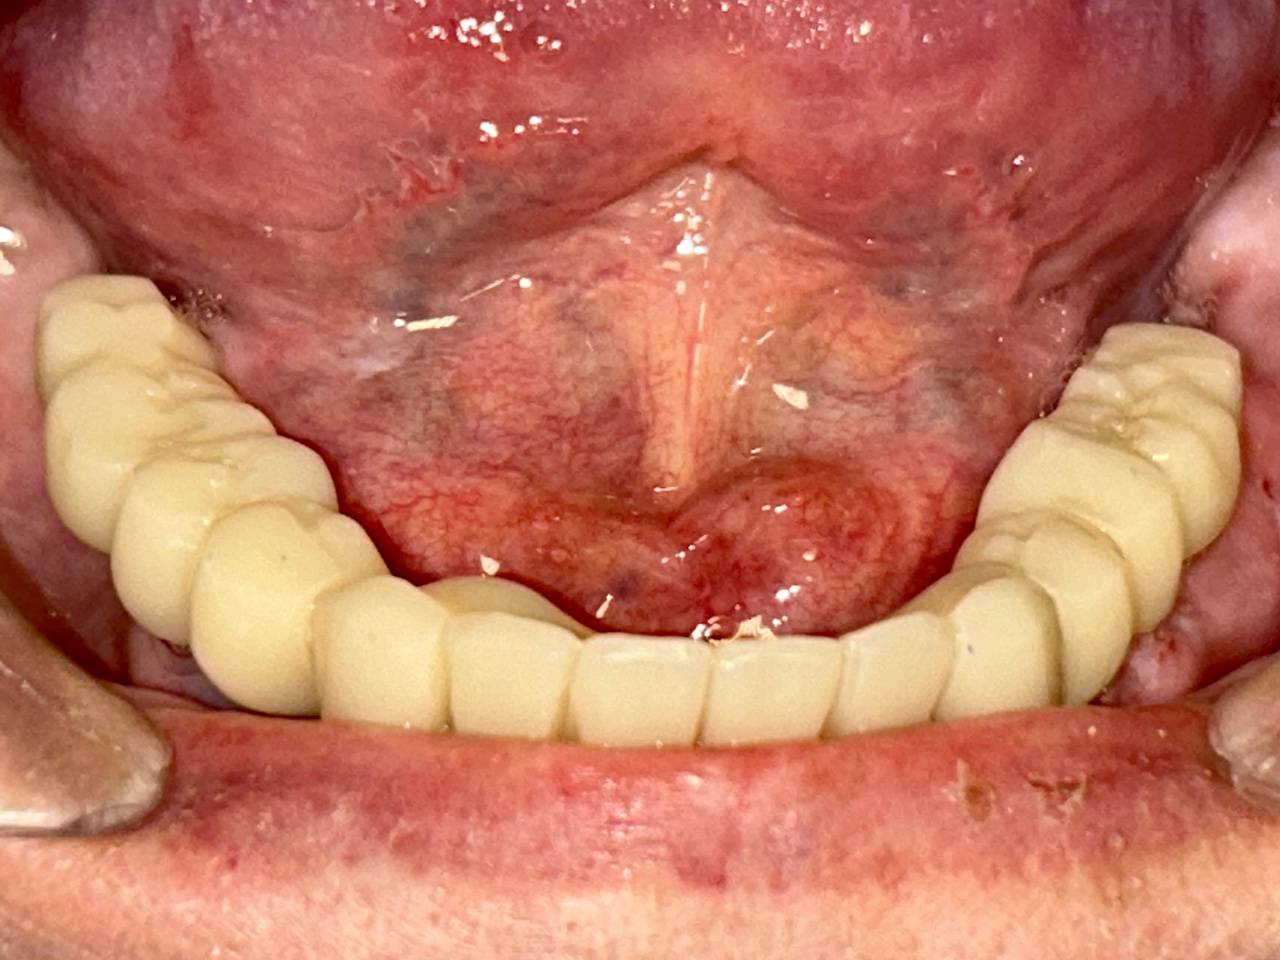

Alsó állcsont teljes rehabilitációja 72 óra alatt

Alsó állcsont teljes rehabilitációja 72 óra alatt, azonnal terhelhető implantátumokkal súlyos paradontitisben szenvedő dohányzó páciens esetében. Az alsó állcsont fogai mind mozogtak az előrehaladott fogágypusztulás miatt.

A fogakat eltávolítottuk, a gyulladt, fertőzött csontot kitakarítottuk, kifertőtlenítettük, majd azonnal implantáltunk.

Svájci, IHDE márkájú, azonnal terhelhető implantátumokat helyzetünk be, és ezekre harmadnapra rögzített, hosszútávú, fémvázas, esztétikus műanyaggal leplezett hidat ragasztottunk be.

Ezt az ideiglenes hidat a sebek gyógyulása miatt használjuk, de tartóssága miatt véglegesként is használható. A legtöbb esetben, ahogy itt is, 6 hónap múlva porcelán hídra cseréljük, a teljes gyógyulás után.